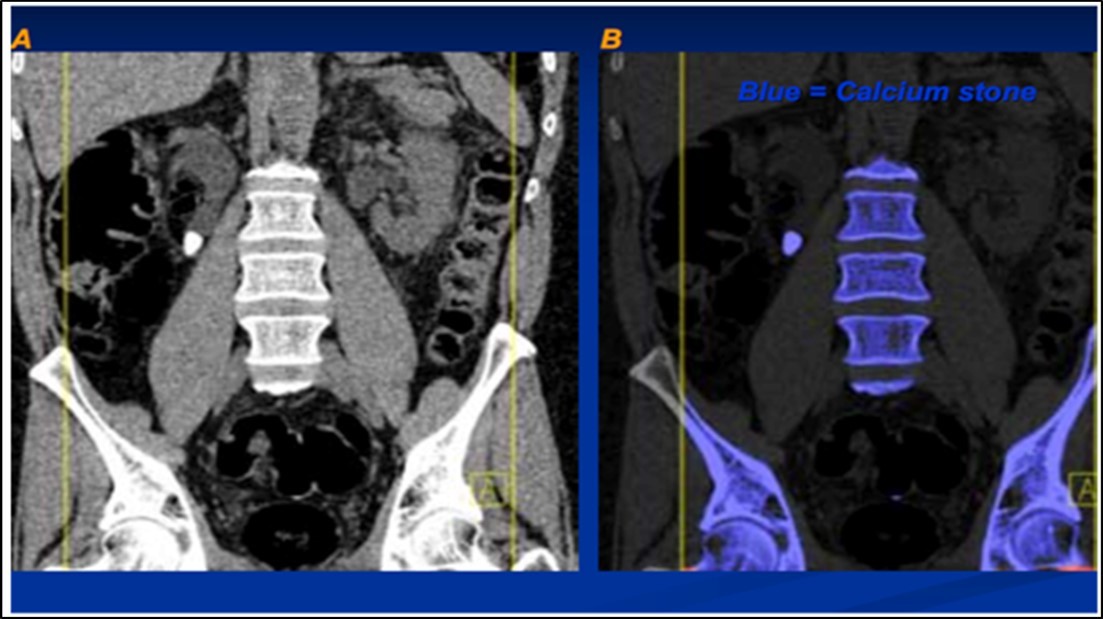

The attenuation difference is shown in colors. In graph 1, the 1.15 ratio represents threshold between uric acid and other stones. If a data point corresponding to a stone with unknown composition falls below this line, the algorithm will characterize such stone as a UA stone and will assign it a predefined red color. And if it falls above the line it will be identified as a non-UA stone and will be shown blue 2.

Stone analysis, together with serum and 24-hour urine metabolic evaluation, can identify the etiology in more than 95% of patients 1. Preoperative prediction of stone type (figure 1 and figure 2) is crucial for therapeutic decision making and follow-up 2, 3, 4, 5, 6. Some studies have reported predictive role of dual energy CT scan for determination of stone type 7, 8, 9.